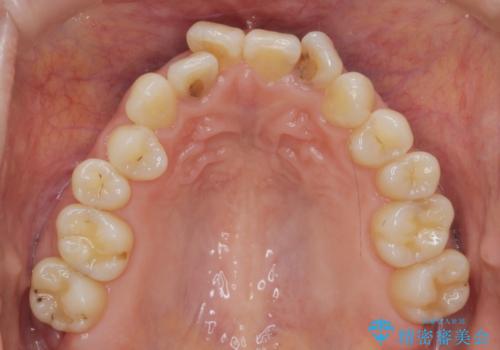

前歯の目立つガタつきをマウスピース矯正で治療

- 大きく傾いてしまった前歯のガタつきの改善を求めて来院されました。

前歯のガタつきをしっかりと取り、機能的・審美的に理想的な歯並びをマウスピース矯正で達成します。

強度のガタつきはマウスピース単体では並び切ることが難しいこともありますが、しっかりと装着していただいたことで良好な治療結果を得ることができました。